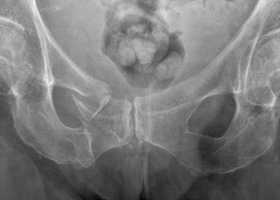

Рентгенограмма при переломе костей таза

- Рентгенография костей таза.